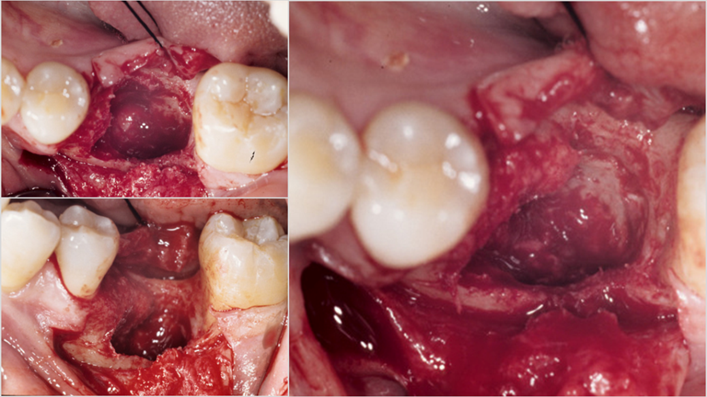

Clinical case: Bone growth in deepest thread of 8.0mm AnyRidge fixture

- Courtesy of Dr. Kwang Bum Park -

Keywords

AnyRidge, KnifeThread, extraction socket, initial stability, allograft, osseointegration, Dr. Kwang Bum Park, mandibular posterior, single replacement, Mega-Oss

Products:

Implant system-AnyRidge, Regeneration-Mega-Oss